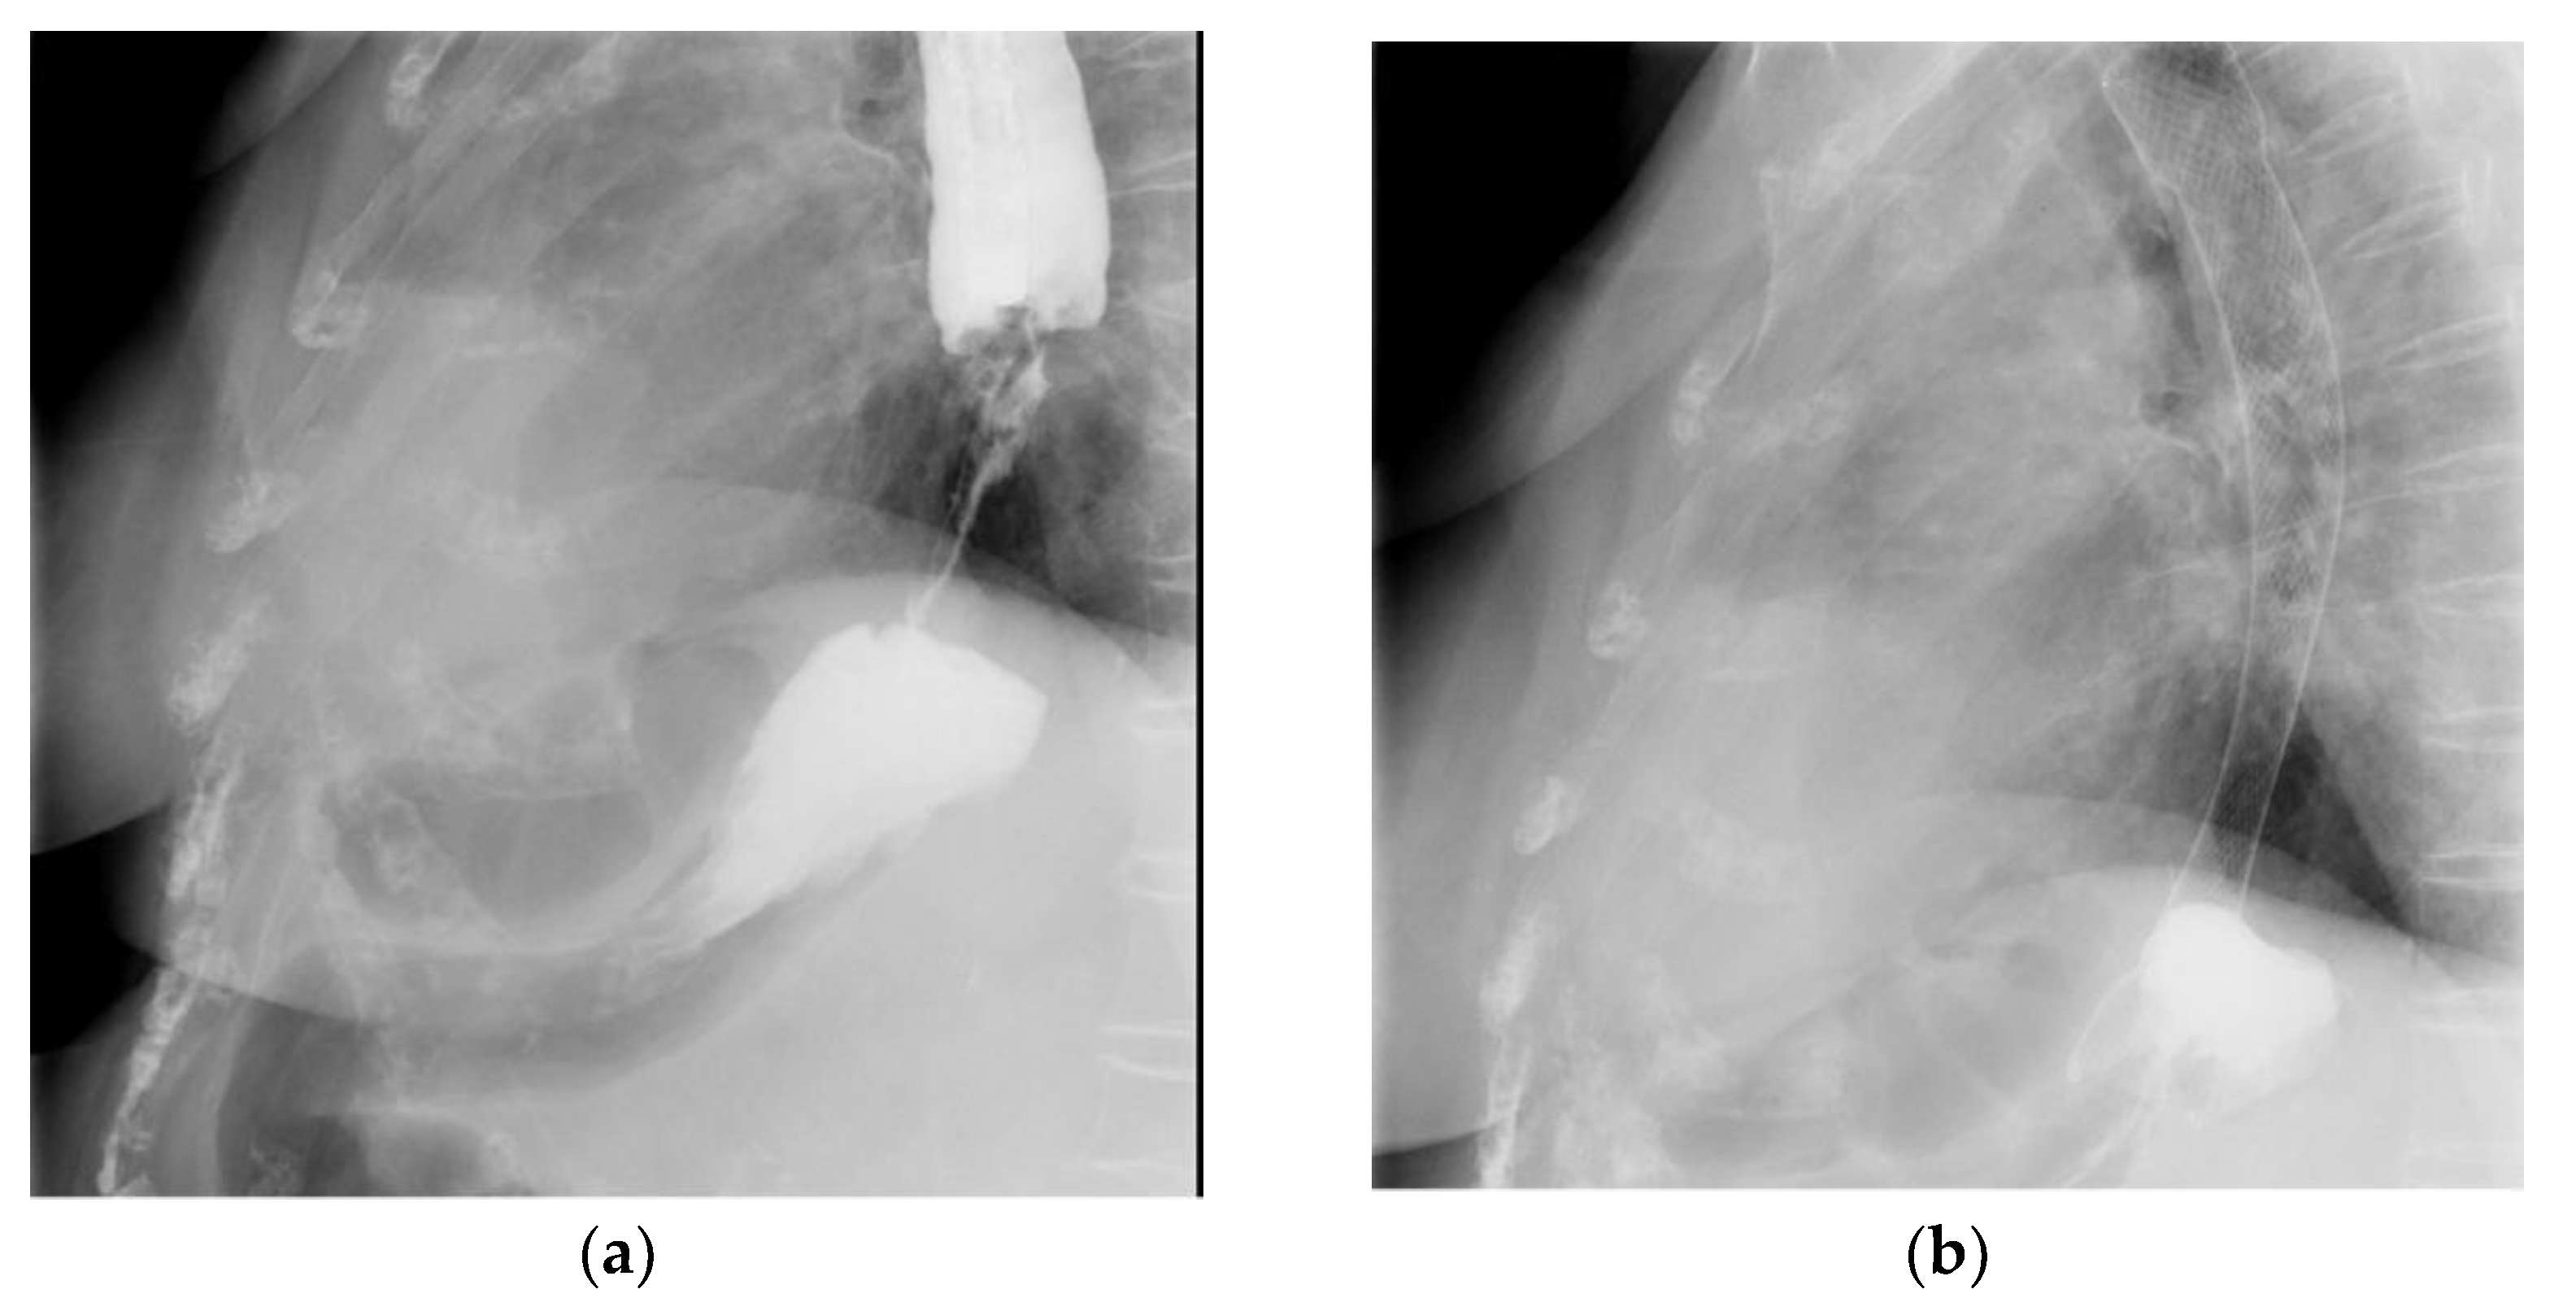

2.5. Esophageal Stents